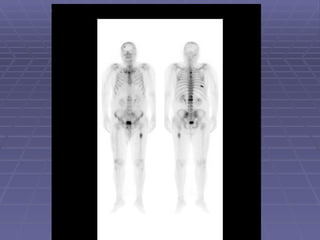

Stress Fractures   It is often difficult to visualized on a plain radiograph. Fractures may be identified by bone scan as early as 24 hours after occurrence. 3-phase bone scan is usually done.  There is hyperemia and osteoblastic process (three phases are positive).

• #33 57 year old man with painful left ankle. Plain films showed an area of sclerosis at the distal left tibia. Pertinent Findings: Blood flow images demonstrate an increase in activity in the distal left tibia. The bone scan shows increased activity along the anterior cortex and at the site of sclerosis. Diagnosis: Insufficiency fracture of the distal left tibia. Discussion : Stress fractures are either insufficiency or fatigue fractures. Insufficiency fractures occur in the setting of normal stress applied to abnormal bone. Abnormality of bone includes diminshed elasticity, deficient mineralization. Fatigue fractures result when abnormal stress is applied to normal bone.

• #34 Clinical History: Pain in the right foot for three weeks. Findings: Nuclear Medicine Bone Scan: A single focus of increased radiopharmaceutical activity is identified on all three phases within the distal right fourth metatarsal. Diagnosis: Stress fracture. Discussion: A stress fracture is the result of repetitive, prolonged muscular action on a bone that has not accommodated itself to that action. In most instances, persons who have stress fractures are engaged in vigorous activity to which they have not yet become conditioned. Under normal circumstances, the muscle tone takes up at a faster rate than bones which result in a mechanical imbalance. Stress fractures are divided into two categories, fatigue fractures and insufficiency fractures. A fatigue fracture is caused by the application of abnormal stress or torque on a bone that has normal elastic resistance. On the other hand, an insufficiency fracture occurs when normal muscular activity stresses a bone that is deficient in mineral or elastic resistance. The term pathologic fracture should be reserved for fractures that occur in bone already weakened by neoplasm or infection. The stress placed on bone causes resorption and microfractures. If the patient rests and the stress decreases then repair may continue with resultant relief of pain. However, if the repair process can no longer keep up with the resorptive process, then cortical disruption and a radiographically visible fracture may ensue. Findings develop earlier on bone scan and MRI than on plain film roentgenograms. A hot spot on all three phases of a bone scan is a bone that has received repetitive trauma is indicative of a stress fracture. Type sites for athletic stress fractures include:Tibial and fibular shaft ;Medial aspect of the femoral neck ;Inferior pubic ramus ;Metatarsals and os calcis ;Navicular and tarsal sesamoids